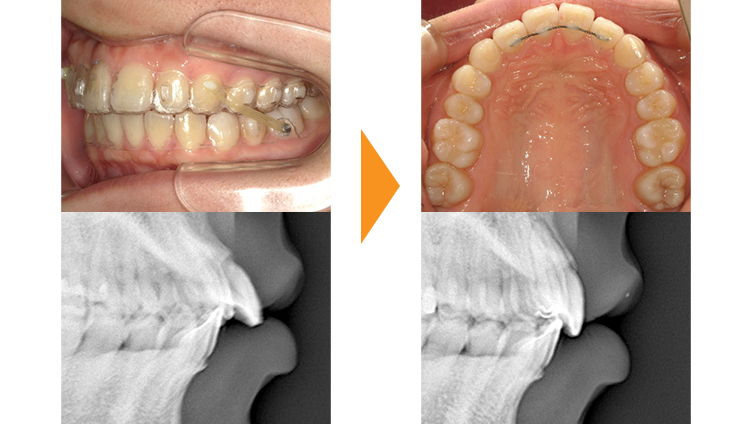

大学4年生で就職による転居の可能性もあったため、短期間で終わる部分矯正を行うこととしました。就職活動への影響も不安に思われていたためインビザラインでの部分矯正を選択されました。

下顎は動かさないですが出っ歯を改善するための支えとするためインビザラインのマウスピースは上下とも入るようになります。

顎間ゴムの使用の協力性も良く上顎前歯が中に入り、すきっぱもきれいに改善し大変喜んでいただけました。

下顎は動かしていないため、上顎を中に入れられる限度は下の前歯の位置までとなります。

すきっぱは後戻りがしやすい歯並びなので、矯正後は歯の裏側からワイヤー固定を使用し、マウスピースも継続して使用する必要があります。

ホワイトニングも行っているため歯の色もきれいになりました。

| 初診時 | 21歳8か月女性 |

|---|---|

| 主訴 | 上の歯の出っ歯とすきっぱが気になる |

| 期間 | 約8か月 |

| 矯正 | インビザライン・IPR・顎間ゴム |

| 費用 | 基本検査22,000円・契約料495,000円・調整料5,500円/月(税込) |

| 治療上のリスク | 歯磨き不良の場合はむし歯になる可能性。 習癖に伴う後戻りの可能性。 |